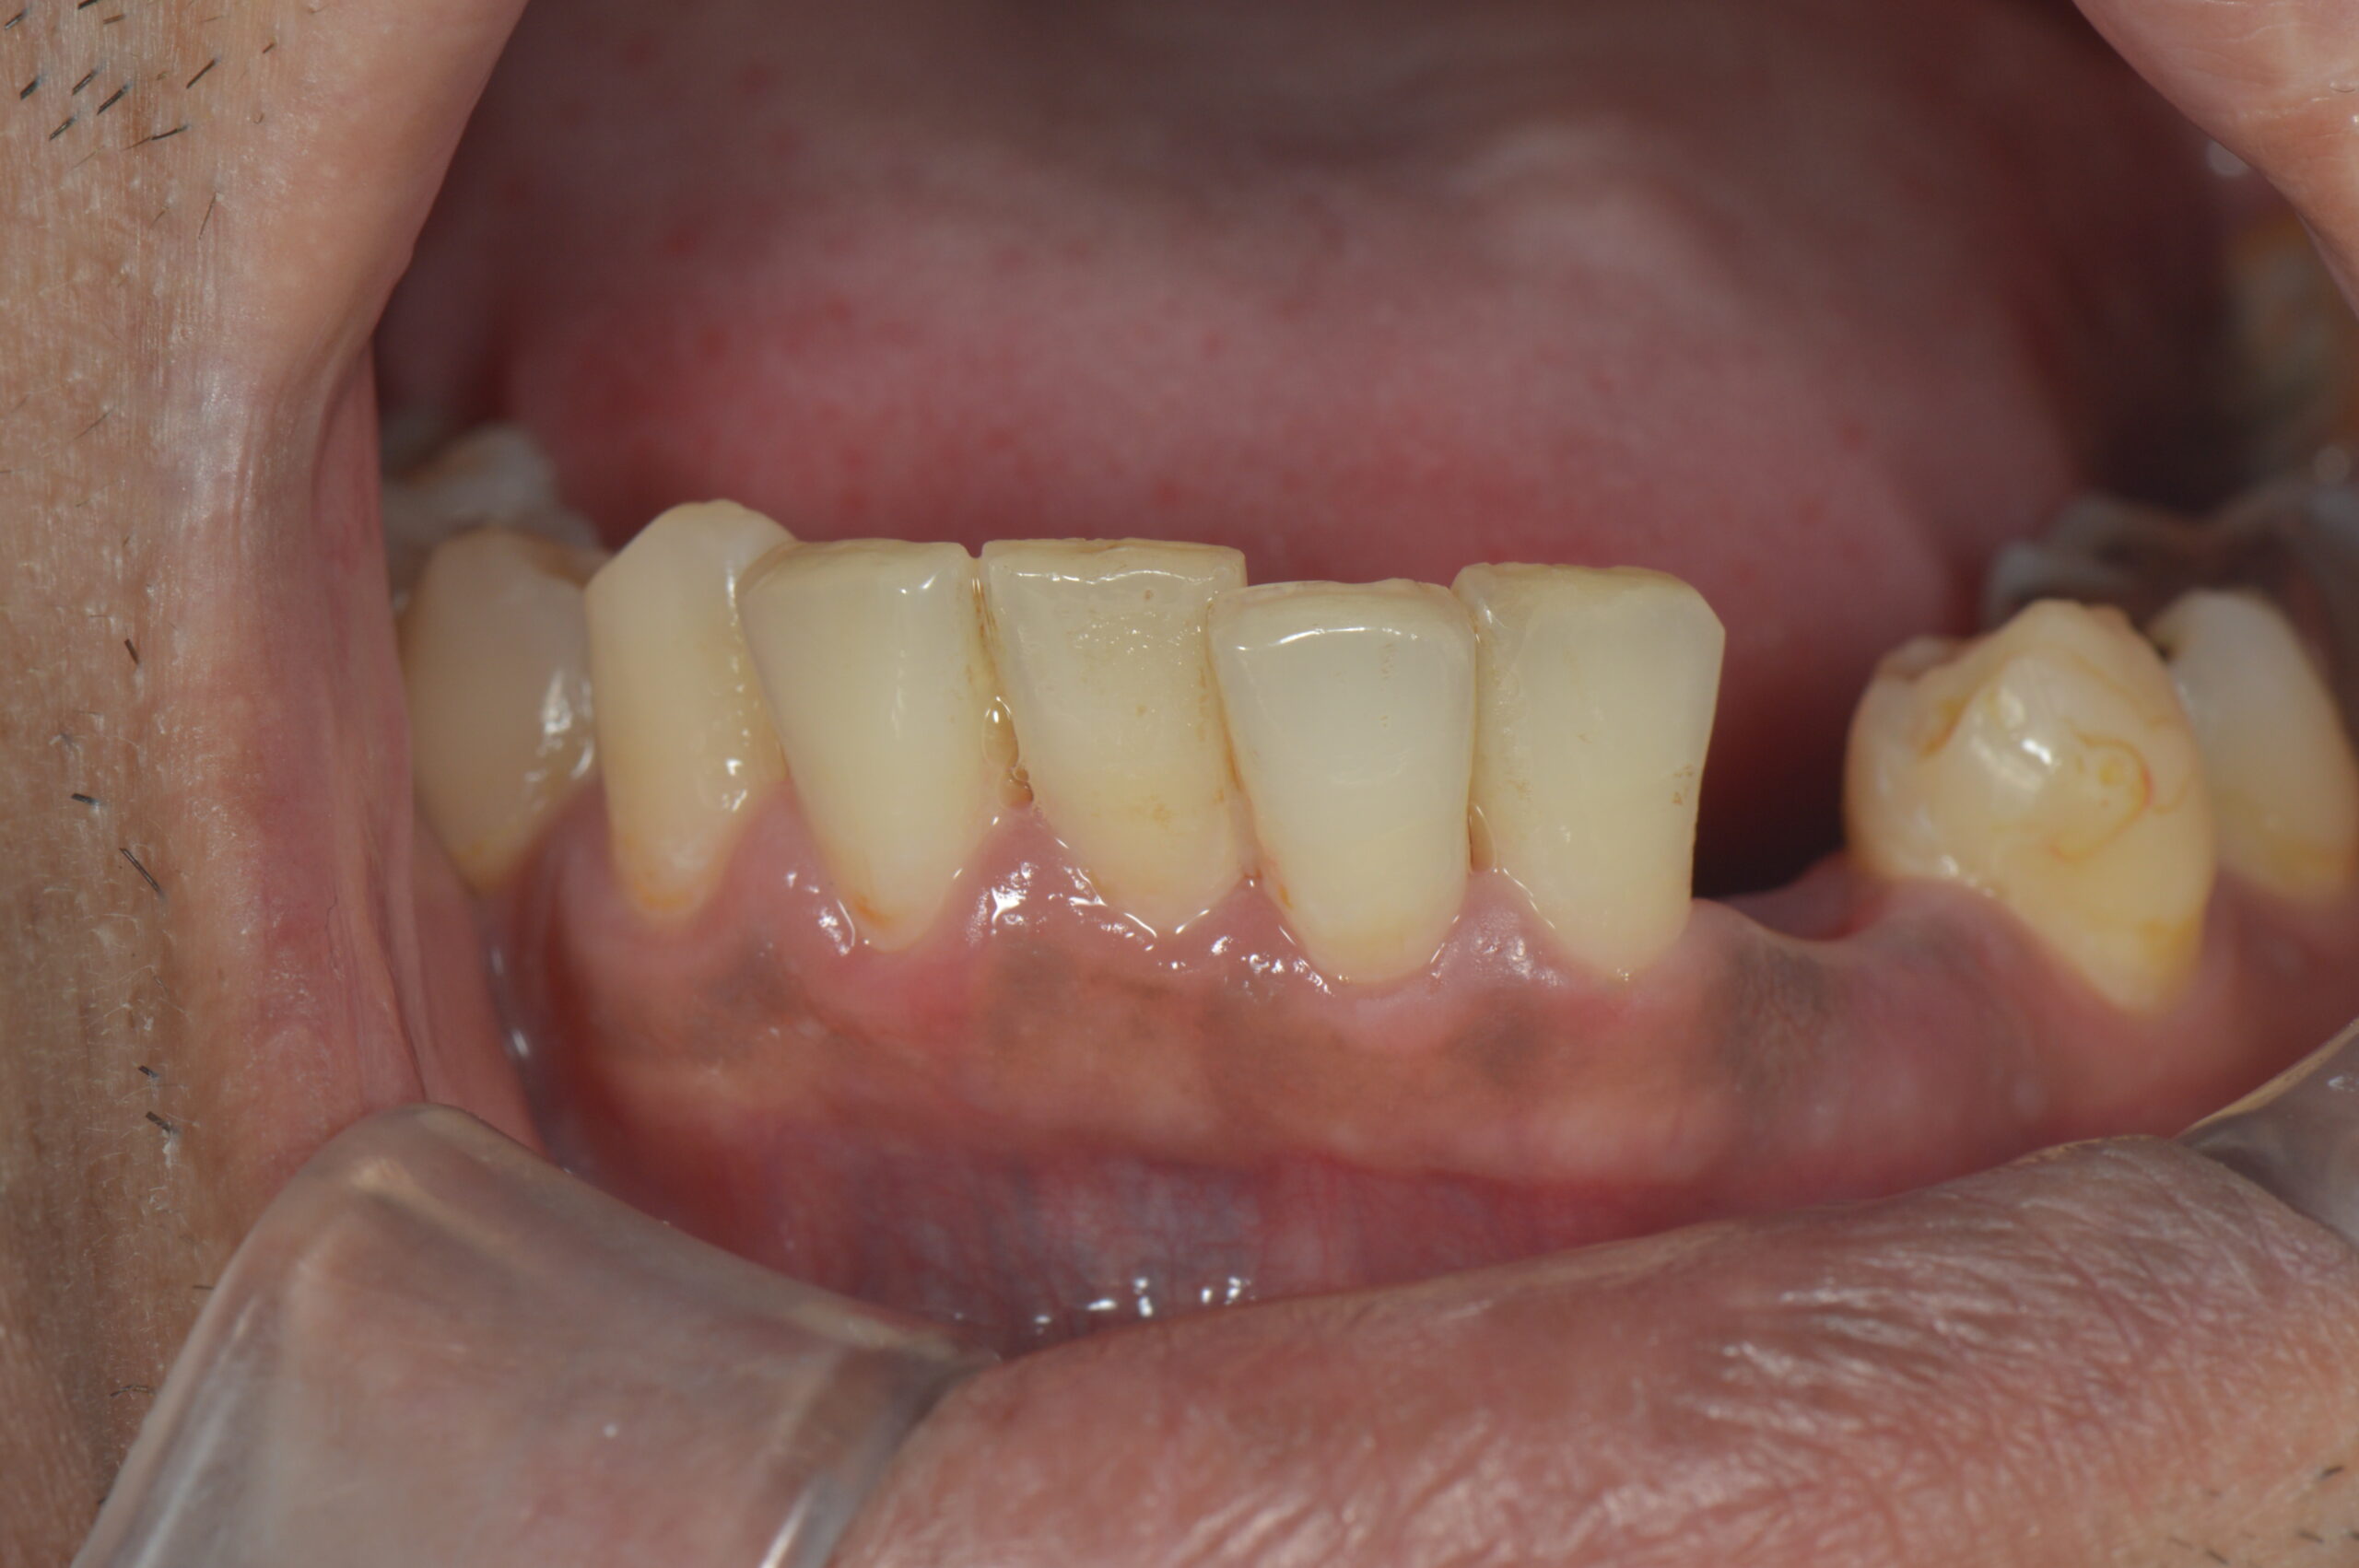

下の写真は、今回ご紹介する患者さんの初診時の口腔内です。事故によって歯が歯肉の際で折れており、歯肉の上に歯質がほとんど残っていない状態です。この状態ではフェルール(被せ物の土台となる歯質の壁)が確保できず、そのまま被せ物を作ることができません。

下の写真は、最終的なクラウン(被せ物)を装着した状態です。歯肉の腫れもなく、歯茎のラインも自然な位置に落ち着いています。機能的にも審美的にも良好な仕上がりとなりました。